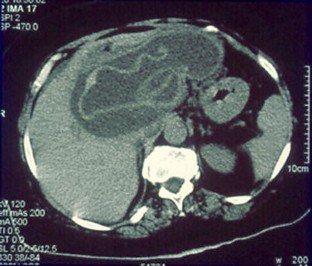

Abb. 1

Abb. 2

Abb. 3

Abb. 4

Abb. 5